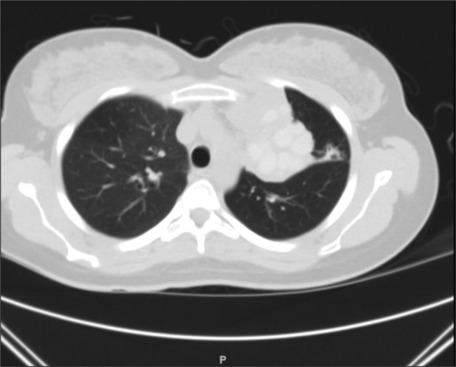

过敏性支气管肺曲霉病(ABPA)是一种由烟曲霉定殖气道引起的超敏反应,主要影响免疫能力强的个体,特别是哮喘患者。ABPA常被误诊为严重哮喘或非缓解性肺炎,导致适当治疗的延误。早期识别ABPA对于预防疾病进展和不必要的抗生素使用至关重要。我们报告一例28岁的女性患者,她有长期控制不佳的哮喘病史,她表现为发烧,咳嗽,放射检查结果最初提示非溶解性肺炎。尽管接受了多个疗程的抗生素治疗,她的症状仍然存在。进一步的调查,包括血清总IgE水平升高、曲霉菌特异性IgE、嗜酸性粒细胞增多和阴性分枝杆菌培养,证实了ABPA的诊断。患者成功接受全身皮质类固醇(强的松)和伊曲康唑治疗,2个月后临床和放射学均有显著改善。她的IgE水平明显下降,支持超敏反应的解决。本病例强调了在哮喘反复发作和不明原因肺部症状患者中识别ABPA的重要性。鉴于有可能被误诊为肺炎,临床医生应保持对ABPA的高度怀疑,特别是在抗生素治疗未能改善的非解决性肺炎的情况下。

Allergic bronchopulmonary aspergillosis (ABPA) is a hypersensitivity reaction triggered by Aspergillus fumigatus colonization of the airways that primarily affects immunocompetent individuals, particularly those with asthma. ABPA can often be misdiagnosed as severe asthma or non-resolving pneumonia, leading to delays in appropriate management. Early recognition of ABPA is crucial to prevent disease progression and unnecessary antibiotic use. We report a case of a 28-year-old female with a long-standing history of poorly controlled asthma who presented with fever, productive cough, and radiographic findings initially suggestive of non-resolving pneumonia. Despite receiving multiple courses of antibiotics, her symptoms persisted. Further investigations, including elevated total serum IgE levels, Aspergillus-specific IgE, eosinophilia, and negative mycobacterial cultures, confirmed a diagnosis of ABPA. The patient was successfully treated with systemic corticosteroids (prednisone) and itraconazole, leading to significant clinical and radiological improvement over 2 months. Her IgE levels markedly decreased, supporting resolution of the hypersensitivity reaction. This case underscores the importance of recognizing ABPA in patients with recurrent asthma exacerbations and unexplained pulmonary symptoms. Given the potential for misdiagnosis as pneumonia, clinicians should maintain a high index of suspicion for ABPA, particularly in cases of non-resolving pneumonia where antibiotic therapy fails to achieve improvement.